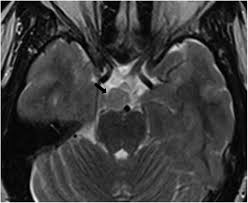

Hypothalamic Hamartoma In Paediatric Patients Clinical Characteristics Outcomes And Review Of The Literature Neurologia English Edition

Hypothalamic Hamartoma In Paediatric Patients Clinical Characteristics Outcomes And Review Of The Literature Neurologia English Edition from multimedia.elsevier.es